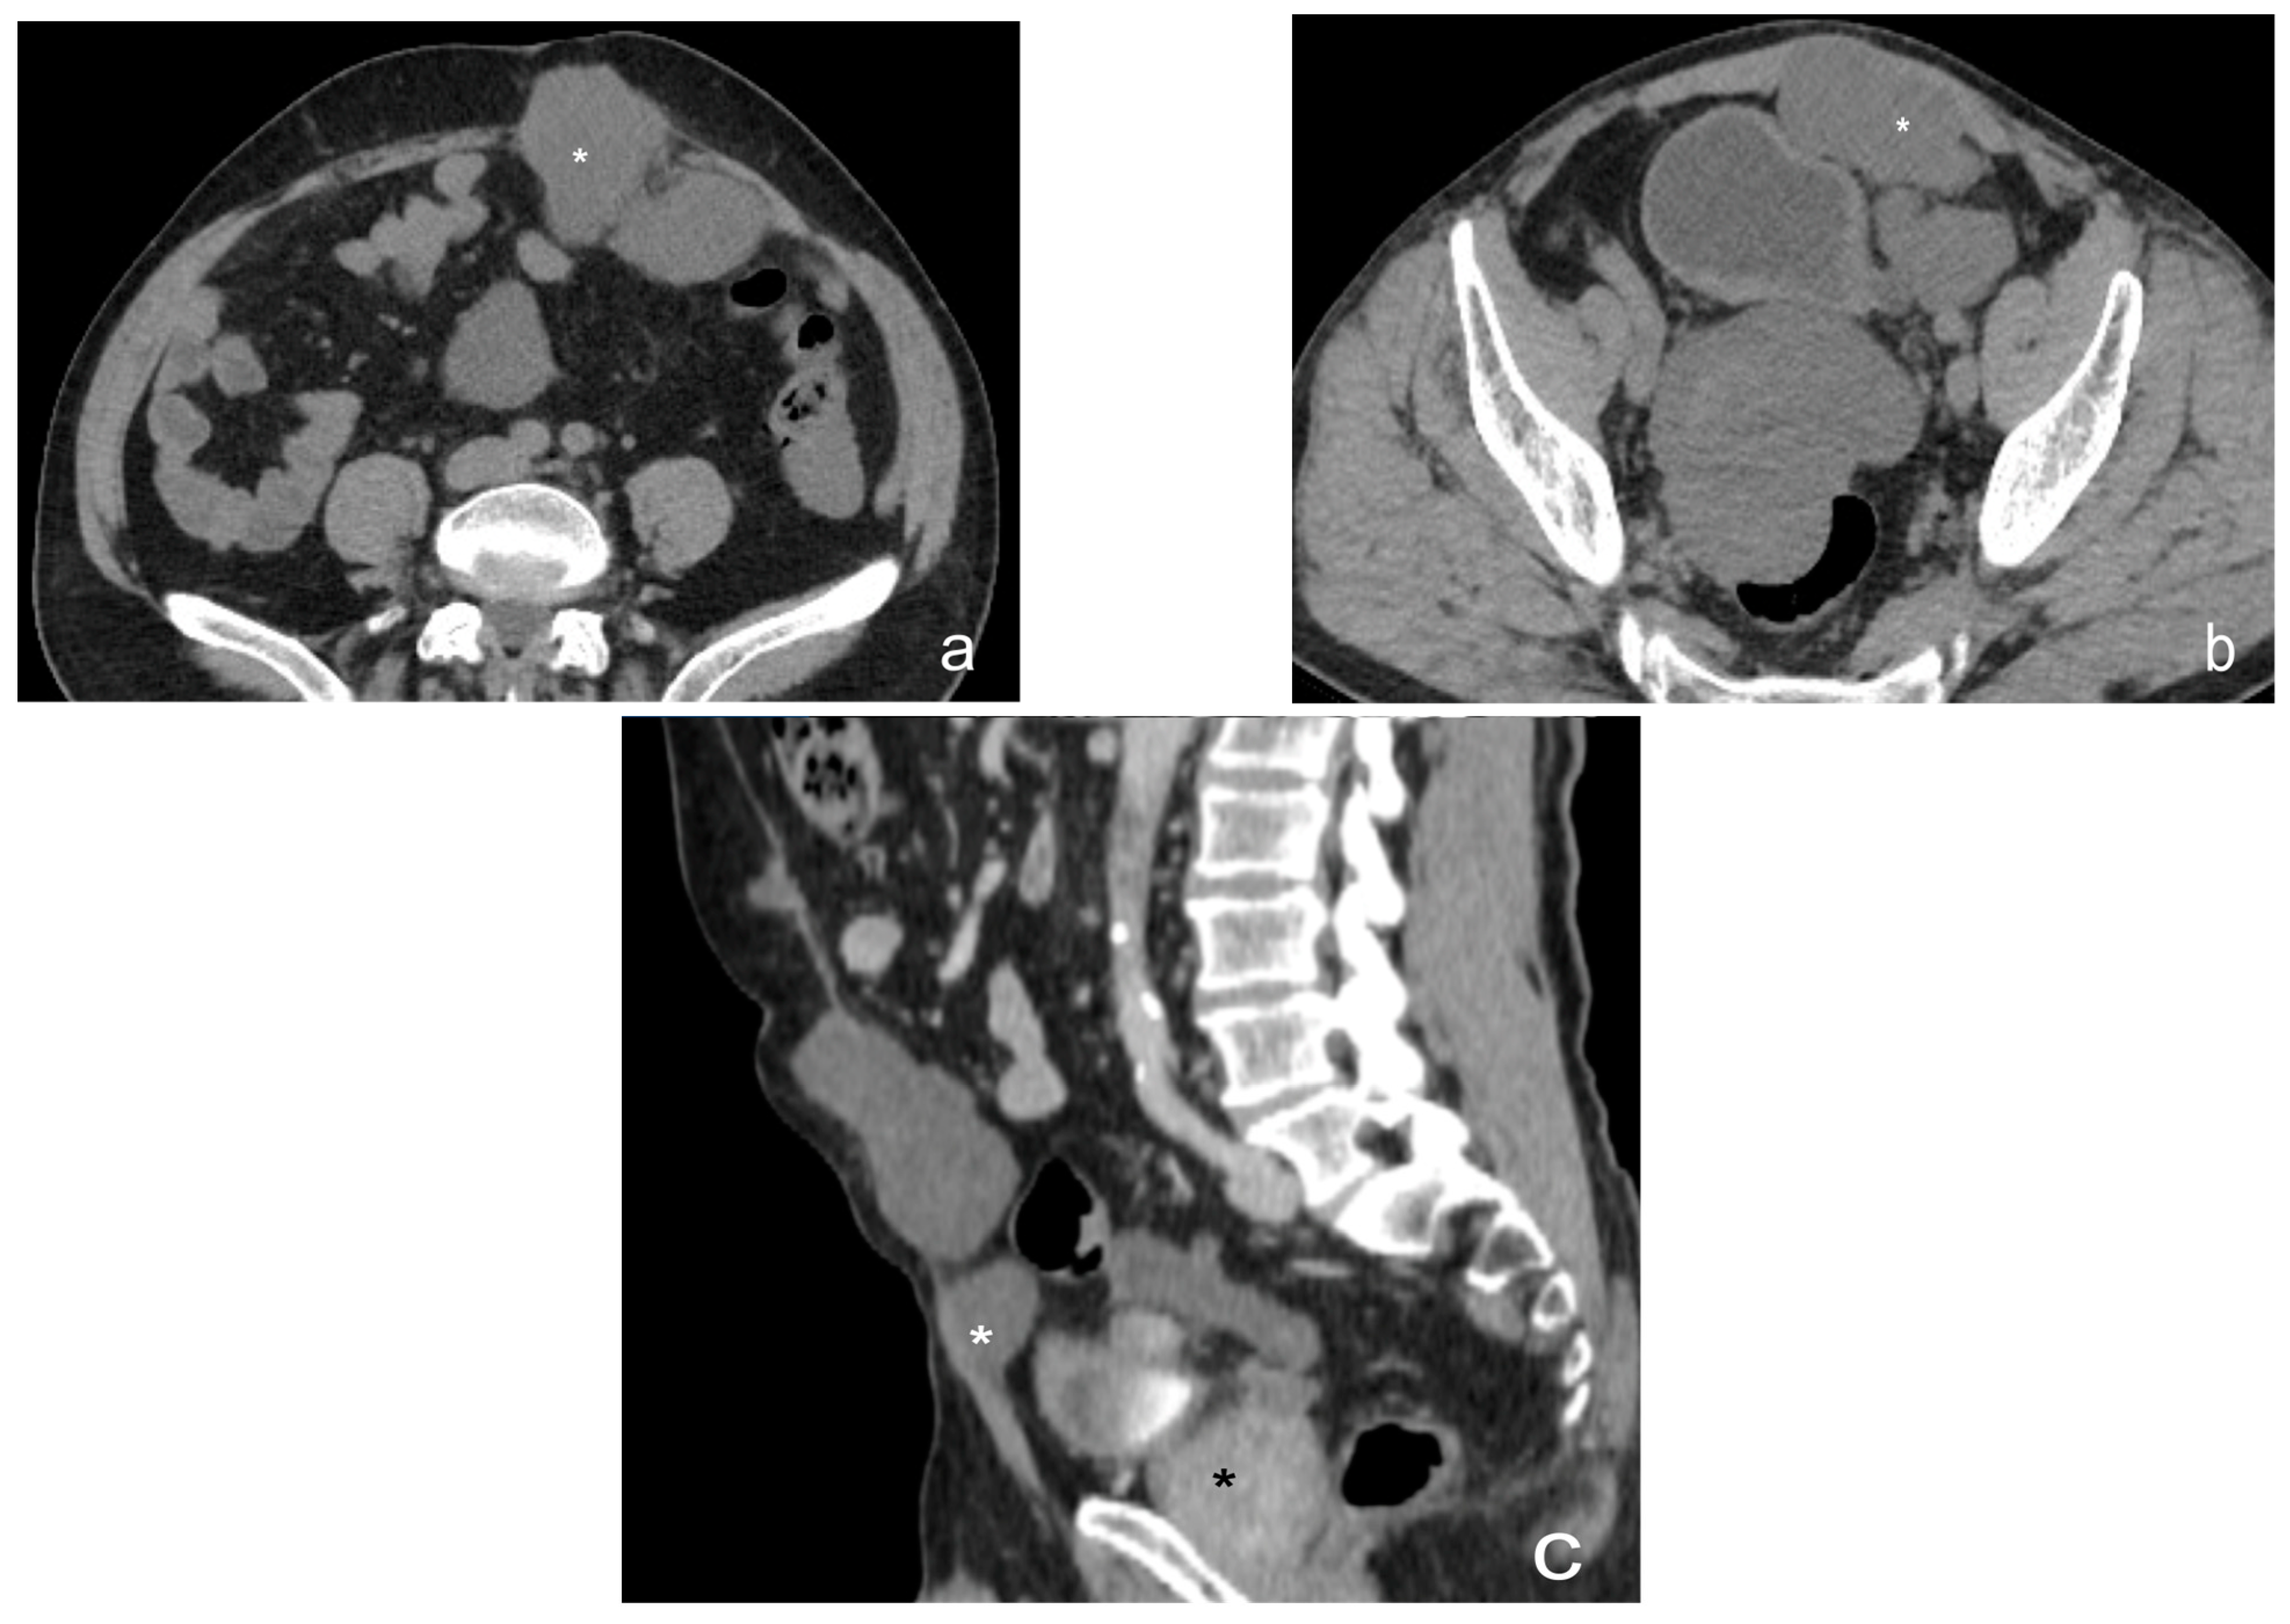

- Plaque pattern: confluent nodular tumor implants that are typically located on the lower surface of the right diaphragm and may manifest as a depression of the liver surface, mimicking capsular or subcapsular liver metastases. They present as areas of low attenuation relative to the parenchyma on postcontrast scans [94,95] (Figure 10).